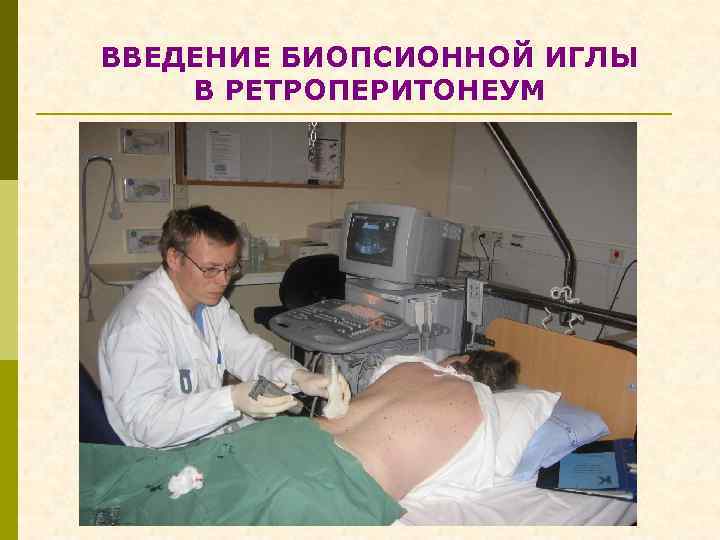

ВВЕДЕНИЕ БИОПСИОННОЙ ИГЛЫ В РЕТРОПЕРИТОНЕУМ